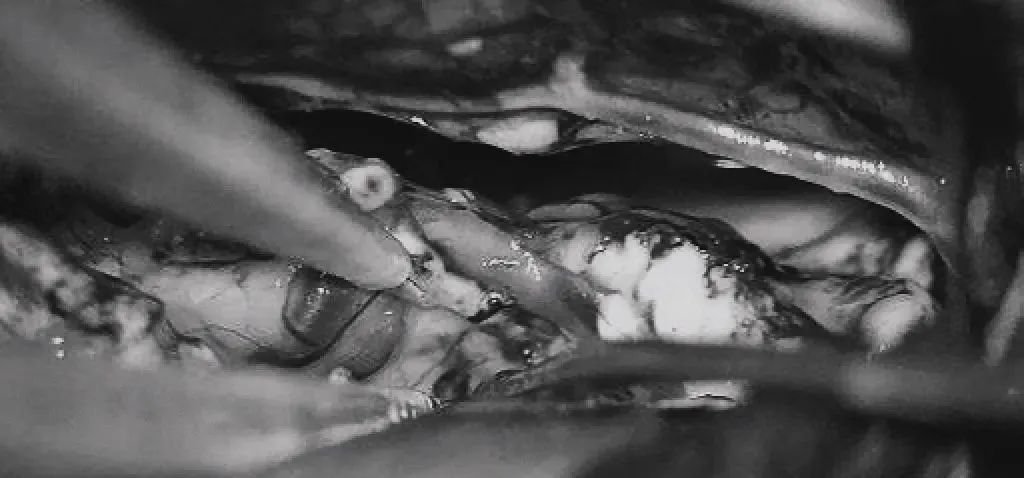

▼将AVM后缘向前牵离穹窿。

▼在透明隔底部保留FoM、穹窿和右侧SepV。

▼引流静脉变黑。

▼引流静脉进入ICV处电凝。完全切除AVM。